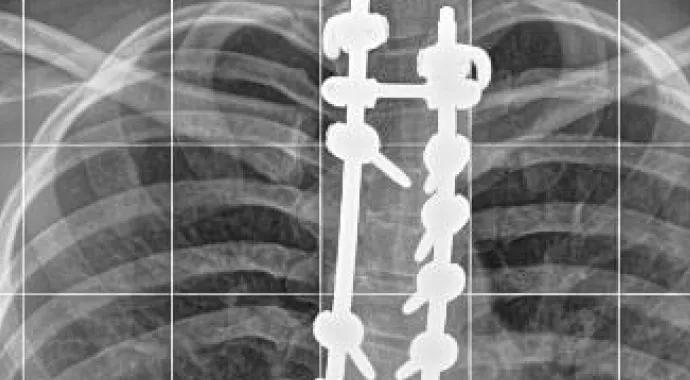

Caption: Standing posteroanterior and lateral radiographs of a 15-year-old female patient three years after posterior spine fusion for scoliosis. She returned to tumbling (photograph) and gymnastics six months postoperatively.

Standing posteroanterior and lateral radiographs of a 15-year-old female patient three years after posterior spine fusion for scoliosis. She returned to tumbling (photograph) and gymnastics six months postoperatively.